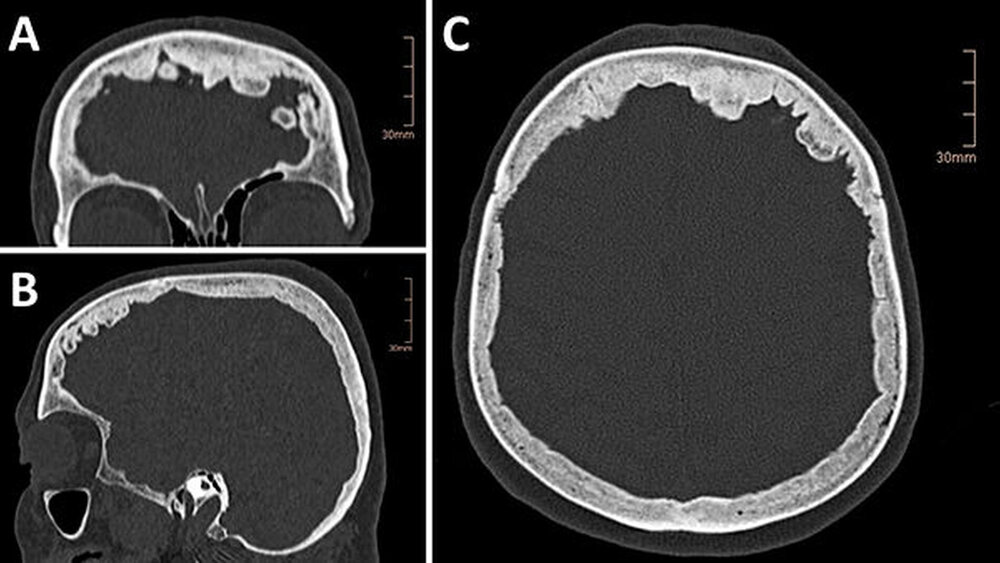

Im erstellten Schädel-CT konnte eine intracranielle Blutung ausgeschlossen werden, jedoch wurde eine ausgeprägte Knochenaposition im Bereich der Facies interna des Os frontale im Sinne eines Morbus Paget (M.Paget) nachgewiesen (Abbildung 1 a bis c).